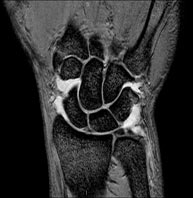

- Wrist / carpus MRI

Examination to study injuries to tendons, muscles and joints. Very useful for assessing minor, otherwise unnoticed fractures, ligament injuries, and inflammatory and degenerative processes (arthritis and osteoarthritis). It lasts approximately 20 minutes. It is a radiation-free procedure.